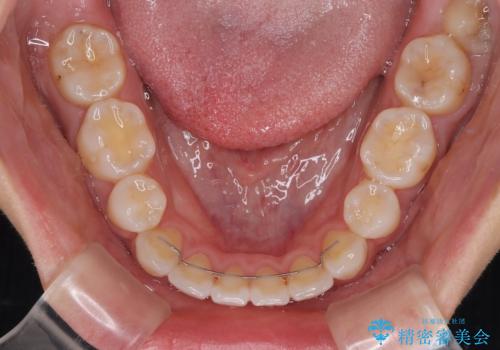

- 矯正装置

- 審美装置

- 前歯が突出して、眠るときに口が開いてしまうことを気にして来院された患者様です。

横から見た際の口元の飛び出した印象も改善したいとのことで、上下左右の第一小臼歯4本を抜歯し、ワイヤー装置にて抜歯矯正を行うこととしました。

舌の突出癖改善のためのトレーニングをしっかりと実践してくださり、2年強の治療期間でしっかりと仕上げることができました。